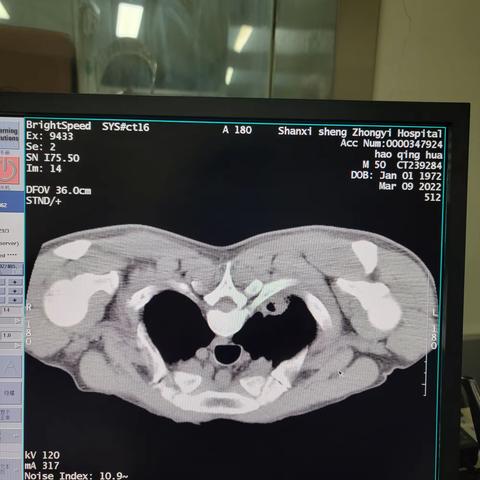

肾盂癌的放射性粒子植入治疗

2022-03-08 926阅读